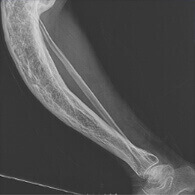

Suyak deformatsiyasi

Chidab bo'lmas og'riq

Falaj

To'liq qobiliyatni yo'qotish

Artrit va artroz Harakat paytida va dam olishda og'riq. Siqilish. Qiyin harakat. Shporlar va kista tuzilmalarining paydo bo'lishi. Qo'shimchaning deformatsiyasi. To'liq harakatsizlik.

Osteoxondroz va osteoporoz Oyoq-qo'llarning vaqti-vaqti bilan uyquchanligi. Orqa va umurtqa og'rig'i. Yurak va qovurg'a sohasidagi og'riq. Servikal mintaqada protruziya va disk churrasi. Qon tomir kasalliklari.

Bursit Shikastlangan bo'g'im hududida kuchli shish. Bo'g'imning harakatchanligi yoki oyoq-qo'lning to'liq harakatsizligi. Palpatsiya paytida og'riqli hislar. Shish sohasida noaniq chegaralar bilan terining qizarishi. Yiringli to'qimalarning shikastlanishi. Qon zaharlanishi. Fistulalarning paydo bo'lishi. Qo'shimchaning motor qobiliyatini to'liq yo'qotish."

Sinovit Harakatlarning qattiqligi. Palpatsiya paytida og'riq. Katta bo'g'imlarning shikastlanishi. Ta'sir qilingan hududda kuchli noqulaylik va shishish. Qon zaharlanishi. Falaj.